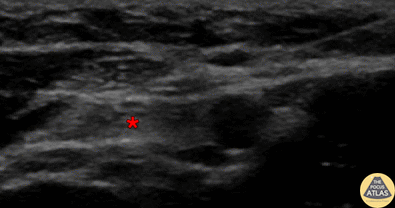

In-plane ulnar nerve block, with needle seen entering from screen right (radial aspect), with anesthetic deposited superficial to ulnar nerve (*). The ulnar artery can be seen pulsating screen right of (radial to) the nerve. Denver Health Ultrasound Fellowship Archive